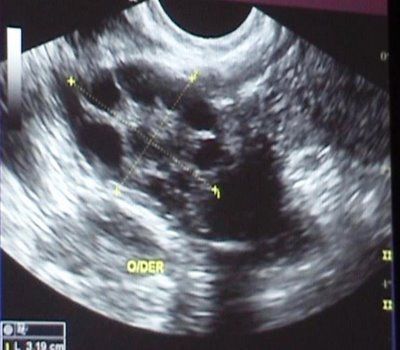

Síndrome del Ovario Poliquístico.